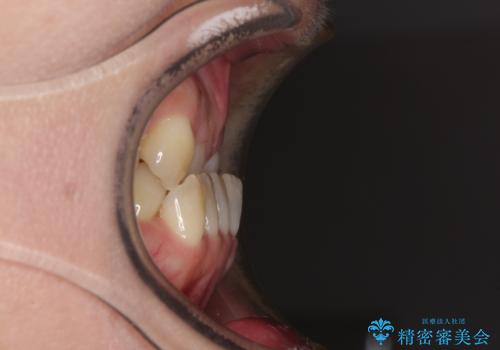

急速拡大装置 前歯の反対咬合をインビザラインで改善

- 前歯の反対咬合を気にして来院された患者様です。

上顎骨の幅が下顎骨よりも小さいので、拡大装置により骨幅を広げて上下関係を改善すると同時にワイヤー矯正で反対咬合の改善を図り、その後インビザラインにて歯並びを整えることとしました。

急速拡大装置の使用により奥歯の咬み合わせが劇的に変わり、その変化を利用して反対咬合を改善することができました。